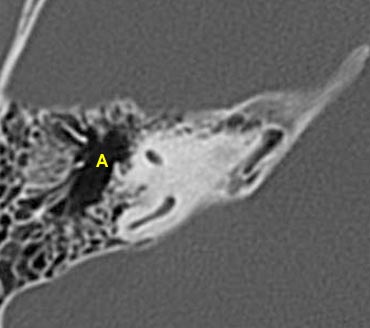

- A = Hang chũm (Antrum)

Trong hình ảnh này ở mức ống tai trong, đoạn nhĩ của dây thần kinh mặt được thấy nằm ngay phía trong và song song với thành của thượng nhĩ.

Ở mức này, ống thông hang (aditus ad antrum) được thấy rõ. Đây là đường thông nối giữa hòm nhĩ và hang chũm.